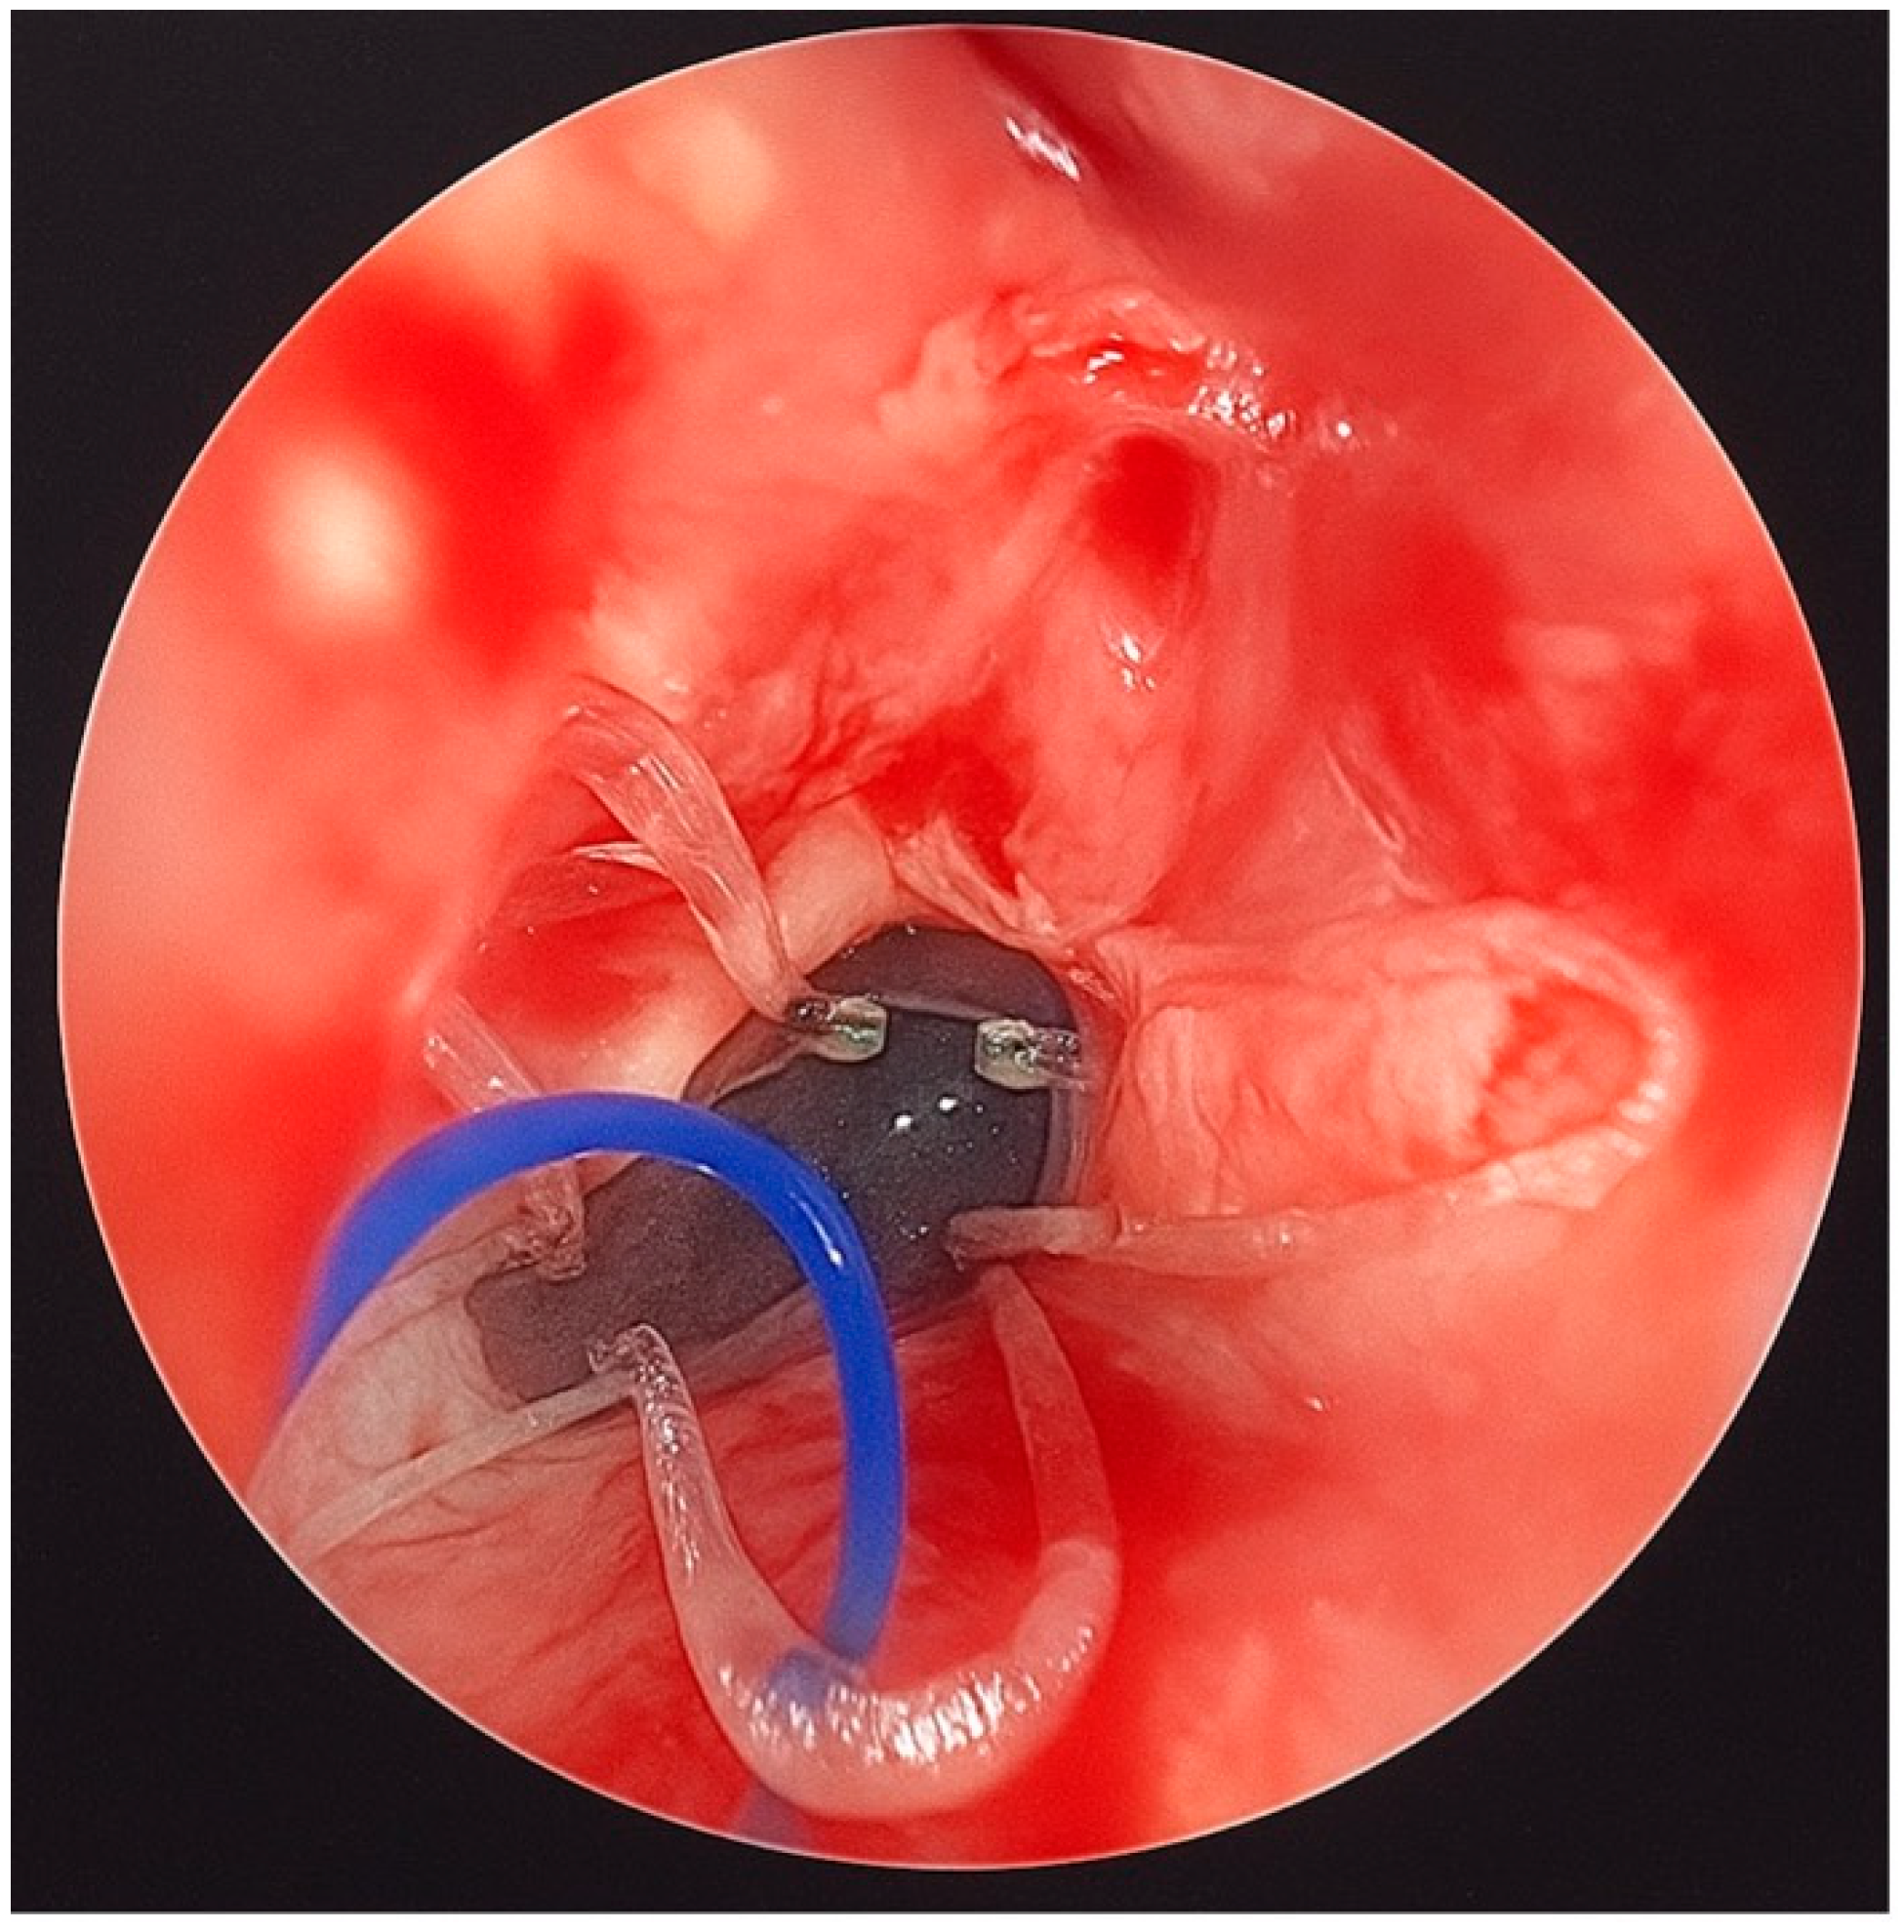

CT imaging confirmed bilateral choanal atresia, as demonstrated by the interruption of the air column on both sides. No bony abnormalities were detected, and the observed membranous appearance was attributed to incomplete physiological ossification of the planum ethmoidalis (Figure 1).

Figure 1. Skull CT highlights the presence of a bilateral membranous septum involving both choanae. The air column was interrupted on both sides; no bone changes were detectable, normal membranous appearance was due to incomplete physiological ossification of the planum ethmoidalis. There was no ethmoidal encephalocele. L: Left; R: right.